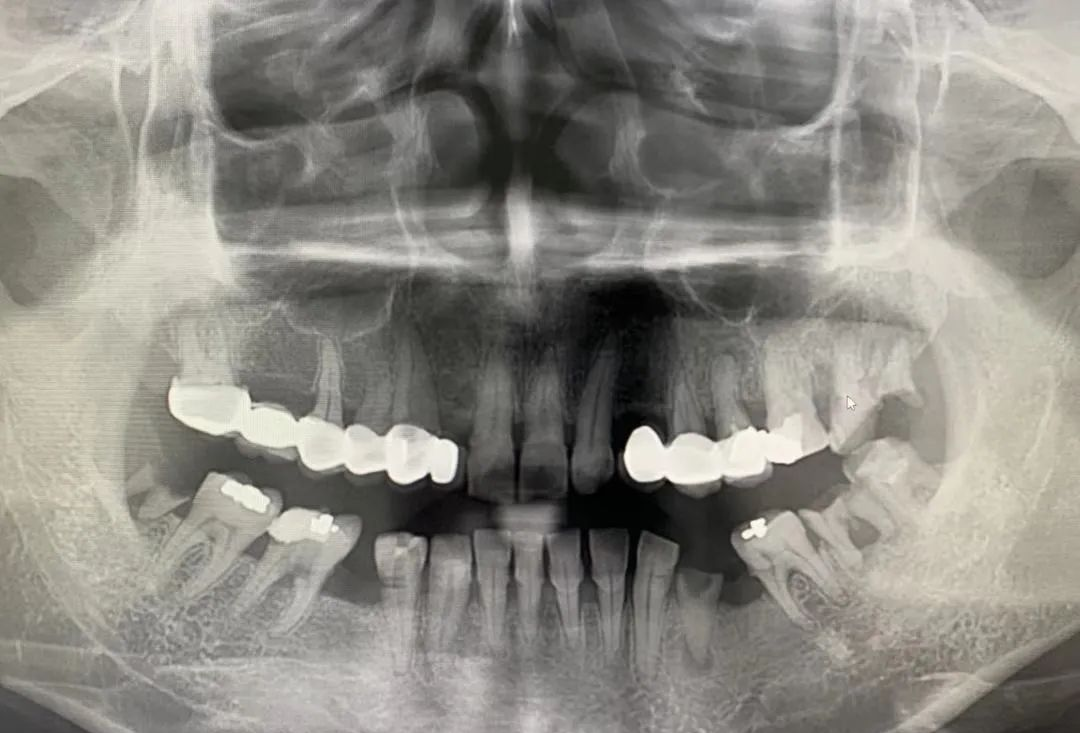

CBCT 是目前国际最先进的口腔专用CT,在业界被誉为神奇的“慧眼”,具有扫描快、范围大、精度高、应用广、辐射量低的特点。可以通过其强大软件处理功能以及面部匹配技术迅速形成清晰逼真的三维图像,较传统CT对于牙齿及颌骨组织的结构成像质量更高,彻底解决了口内牙片机、口腔全景机等口腔X射线设备影像重叠、畸变的问题,可以便捷直观地发现多种牙齿隐患问题,为口腔医生提供精准的诊断与治疗依据。

1、口腔颌面外科方面:用于肿瘤、囊肿的范围及与上颌窦及下颌神经管的关系,颌骨骨髓炎的诊断,骨折的诊断及术前指导,阻生智齿的诊断及拔除指导,多生牙及埋伏牙的定位及毗邻关系,颞下颌关节病的诊断等。

2、牙体牙髓方面:可以清晰观察根管的数目及形态、能够发现变异的细小根管、早期的根尖炎症、牙根折裂等情况。

3、牙周病方面:可以确定牙周病的病变程度及指导治疗。